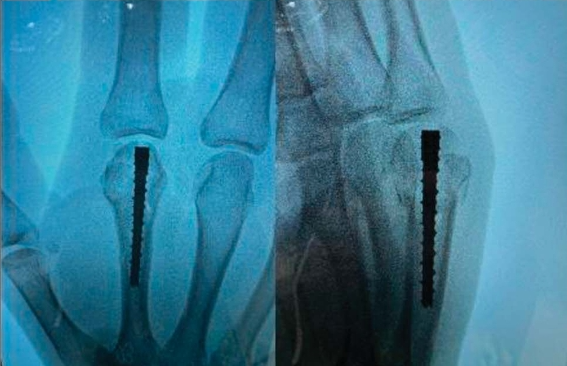

2. Intramedullary Screw Fixation for Metacarpal Head Fractures

Intramedullary Screw Fixation.png

Intramedullary Screw Fixation 2.png

Intramedullary Screw Fixation 3.png